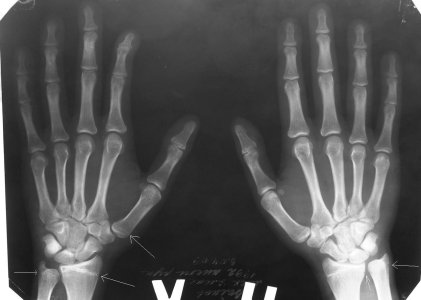

Снимки кистей:http://s60.radikal.ru/i168/0902/a4/f0658f969e1e.jpg

Мне сказали что зоны роста закрыты. Но недавно,при приближении снимка, я заметил вот эту красную штуку (зону роста) :

Может быть зоны роста еще не закрыты, а просто плохо просматриваются? Заранее спасибо за ответ.